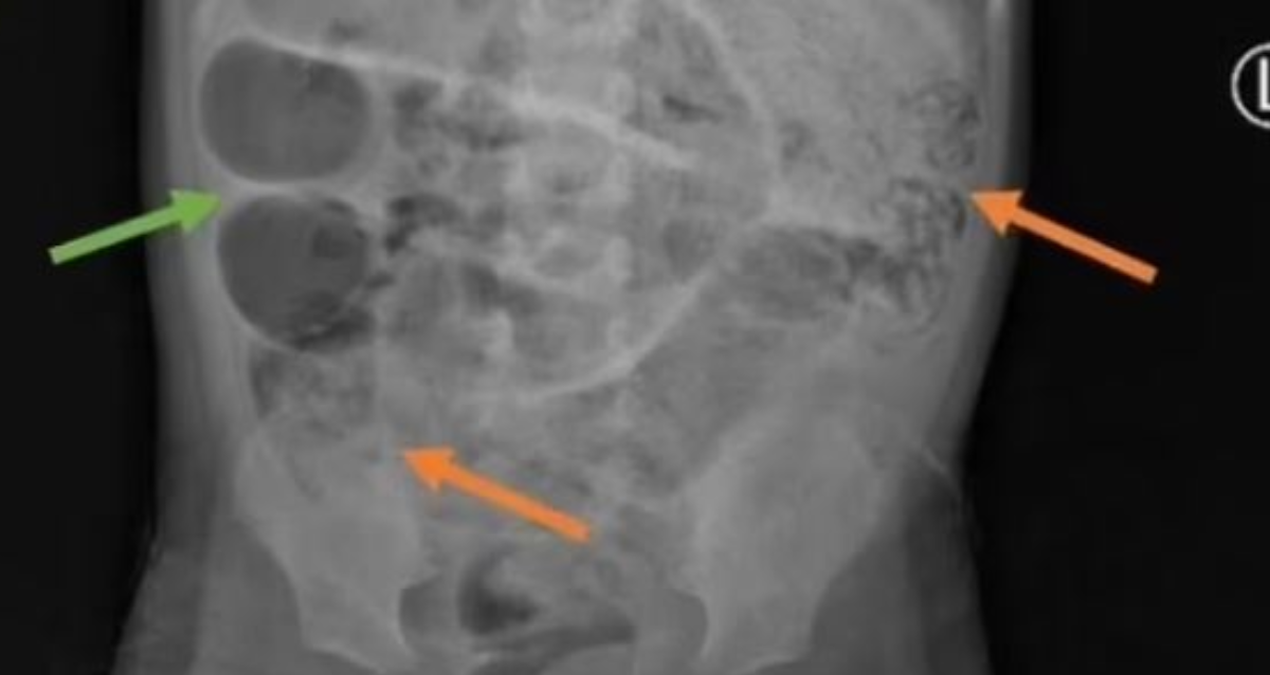

Endonezya’da aylarca mide ağrısı, kabızlık ve ateşlenme sorunu yaşayan 3 yaşındaki çocuk, bir süre sonra kurt kusmaya başladı. Karın şişliği ile hastaneye kaldırılan çocuğa röntgeni çekildi. Gri kitlelerin görüldüğü röntgende kurtların ince bağırsağın üç ayrı bölgesini tıkadığı ortaya çıktı.